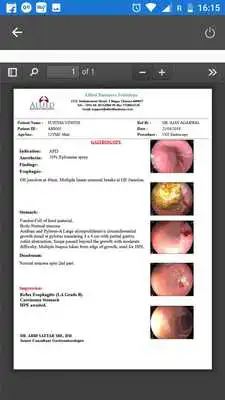

MediView is designed to optimize both time and cost in today's changing and demanding health care scenario. The robust feature coupled with security increase your workflow efficiency by managing patient reports, image and data that enhance patient care.Updates: